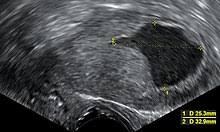

Closer Look At Postmenopausal Bleeding And Endometrial Cancer National Cancer Institute from www.cancer.gov It is the result of the abnormal growth of cells that have the ability to invade or spread to other parts of the body. Endometrial cancer forms in the uterus. The most common symptom for women endometriosis treatment for lung cancer. We have put together a list of common signs and symptoms of. After breast, lung, and colorectal cancer, uterine cancer is the next most common to affect women. Endometrial cancer is often called uterine cancer or cancer of the uterus. Early signs and symptoms of endometrial cancer. Endometrial cancer is often found because it causes signs or symptoms.